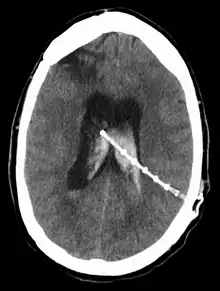

Intraventricular hemorrhage

An intraventricular hemorrhage can occur at any time during or after a shunt insertion or revision. Intraparenchymal hemorrhages that are multi-focal in nature have also been described in the pediatric population following ventriculoperitoneal shunting.[37] The hemorrhage can cause an impairment in shunt function which can lead to severe neurological deficiencies.[34] Studies have shown that intraventricular hemorrhage can occur in nearly 31% of shunt revisions.[38]